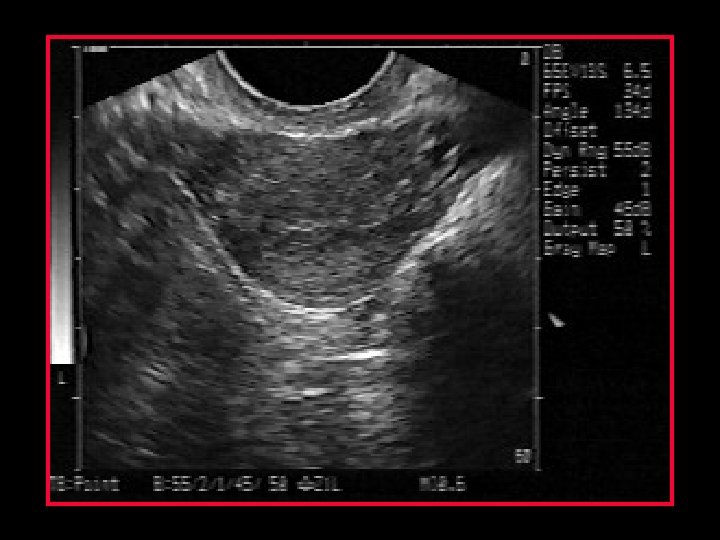

Coronal view